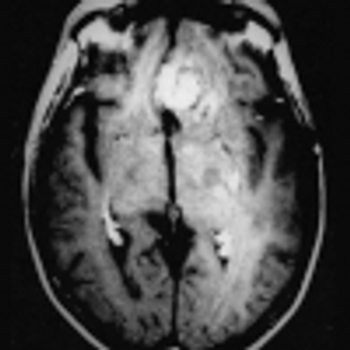

Researchers from Mount Sinai examine and assess the imaging modalities used to evaluate patients positive for the virus.

Research reveals lung findings not typically associated with viral pneumonia.

Affected patients were sicker and more likely to be admitted to the ICU.